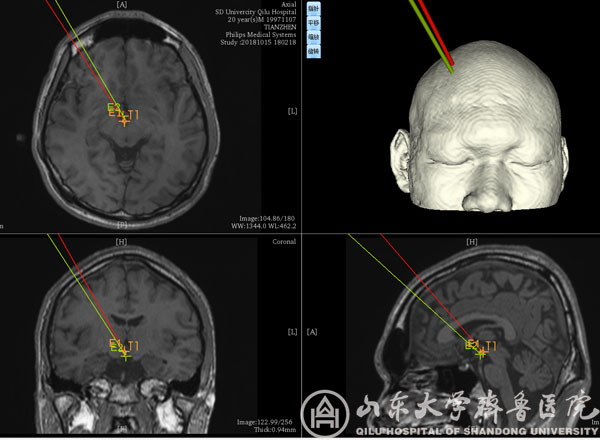

术前计划

手术前后颅内脑电及MRI对比

该患者男,20岁,发作性头痛、痴笑、左眼向上凝视病史11年,口服丙戊酸钠、拉莫三嗪、鲁米那等多种抗癫痫药物效果欠佳,每日痫性发作仍3~6次,颅脑MRI提示右侧丘脑前下部占位性病变,考虑下丘脑错构瘤。患者收入我院功能神经外科病房后,赵秀鹤副主任带领神经内外科团队共同对患者进行了充分的术前评估,对手术方案进行了深入的讨论,考虑到病变位置重要且深在,开放性开颅手术风险高,术后并发症发生率高,最后决定采用立体定向脑电图引导下射频热凝术的治疗方案。10月21日,徐淑军主任、徐硕主治医师为患者制定了SEEG方案,并在手术机器人引导下成功将颅内电极埋藏在预设手术靶点。经术中CT、多模态影像融合技术以及立体定向脑电监测等多种手段验证靶点后,对致痫灶实施精准射频热凝。术后患者癫痫发作频率较术前减少,未见明显不良反应,已顺利出院,长期疗效正在随访观察中。

作为新兴的癫痫病灶诊断与定位技术,SEEG通过埋藏颅内电极的方式精准捕捉致痫灶起源并明确癫痫传播网络,为难治性癫痫的外科治疗提供依据,必要时还可通过电极热凝对位置较深、范围较小或位于功能区的病变进行毁损,发挥治疗作用。由于对定位精准度要求极高(以毫米计算),传统SEEG电极植入主要依靠立体定向框架系统,但手术操作繁琐,耗时较长,且需要在患者局部麻醉下安装立体定向头架,增加患者心理压力。神经外科手术机器人系统通过无框架定位技术与机械臂辅助,在保证手术精度的同时,简化SEEG手术过程,缩短手术时间,改善患者体验。本次手术是手术机器人系统在我院神经外科首次亮相。除SEEG外,未来机器人还有望应用于颅内病变活检、血肿穿刺引流、术中导航甚至脑深部电刺激器植入等神经外科手术。